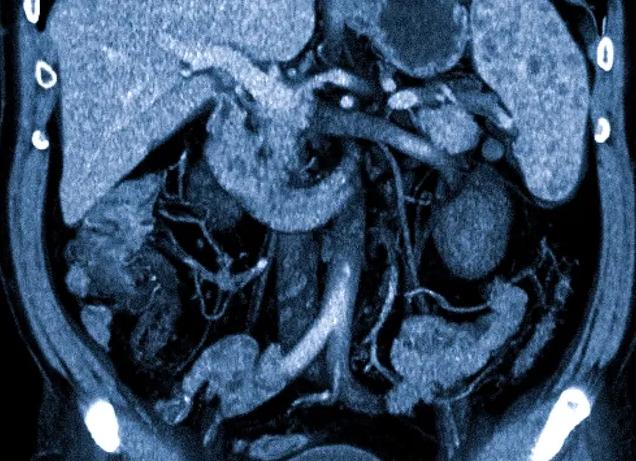

КТ органов брюшной полости

Однако эндоскопическим способом можно осмотреть только слизистую (внутреннюю) оболочку желудочно-кишечного тракта, гастроскопия не позволяет диагностировать патологические процессы в мышечном и серозном слоях, а также состояние окружающих тканей и органов. Если у врача есть подозрение на то, что процесс не ограничивается поражением слизистой, он может назначить КТ.

КТ относится к рентгенологическим методам диагностики, отличаясь от обычного рентгена способом получения информации. Анализатор компьютерного томографа выполнен в виде кольца, внутренняя поверхность которого оснащена рентгеновскими излучателями. Кольцо вращается вокруг стола, на котором расположен пациент, и испускает рентгеновский луч. Излучение, проходя по спирали, делает тонкие сканы органа с интервалом в несколько миллиметров.

В современных аппаратах может присутствовать до шести излучателей по периметру кольца, поэтому они называются мультиспиральные томографы. Применение такой установки помогает повысить диагностическую способность метода, а также выполнить исследование в несколько раз быстрее.

Кроме перорального способа, проводится внутривенное введение контраста, который, достигая стенок органа по кровеносным сосудам, делает их более четкими на томограммах. В качестве контраста при КТ используют рентгеноконтрастные вещества на основе йода.

Для диагностики каких заболеваний необходима компьютерная томография?

Как правило, КТ необходима при раке желудка, а также других видах онкологических процессов этого органа. Коварность злокачественных новообразований заключается в том, что они способны поражать не только орган, в котором начался рост опухоли, но и прорастать в соседние ткани и органы, а также давать отдаленные метастазы (в печень, легкие, головной мозг), эти осложнения не видны при гастроскопии. Поражаются при раке и регионарные (соседние) лимфатические узлы.

КТ позволяет не только выявить распространенность новообразования внутри стенки органа, но и степень распространения процесса в брюшной полости и лимфатических узлах. Также преимуществом КТ перед гастроскопией является то, что выявив патологию в желудке, врач может сразу осмотреть и соседние органы: поджелудочную железу, печень, брюшину.

Такая информация при раке необходима, чтобы онколог мог определить метод лечения пациента, так при начальных стадиях онкологического процесса необходима радикальная операция с удалением опухоли. При раке, который распространился за пределы желудка оперативное вмешательство противопоказано, так как может ускорить рост опухоли, поэтому необходима химиотерапия и лучевая терапия.

КТ информативна не только для диагностики злокачественных новообразований, также как и гастроскопия, она показывает доброкачественные опухоли, полипы, стриктуры и стенозы. Для диагностики язвенной болезни метод применяют редко, так как наполнение органа жидкостью или газом может вызвать осложнения: перфорацию или кровотечение из язвы, поэтому диагностика проводится преимущественно с помощью гастроскопии.